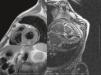

Late gadolinium enhancement (LGE) cardiac magnetic resonance imaging (MRI) is very useful in distinguishing between myocardial infarction, in which the enhancement is typically subendocardial, and myocarditis, in which it is subepicardial (Figure 1). In addition, various patterns have been described with different cardiomyopathies, in some cases enabling a specific diagnosis without invasive workup and risk stratification.1 Cardiac amyloidosis was previously thought to be present only when systemic amyloidosis was patently manifest. This has proved not to be the case, with cardiac MRI detecting increasing numbers of cases in patients with diastolic heart failure in whom cardiac involvement may be the first or sole manifestation. The pattern of LGE commonly found in cardiac amyloidosis is a global subendocardial enhancement with different contrast kinetics, the ventricular cavities showing no signal at all (Figures 2–6) compared to myocarditis and acute myocardial infarction, in which there is an intracavitary gray signal (Figure 1). Of 10 patients referred after echocardiography raised the suspicion of a cardiomyopathy, five were diagnosed with cardiac amyloidosis, two had images not suggestive of amyloidosis and were subsequently found to have Fabry's disease (Figure 7), and the other three probably had concentric left ventricular hypertrophy due to hypertension.